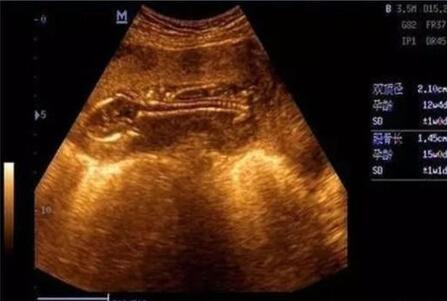

一般来说,B超单上的数据有很多,比如双顶径、腹围、股骨长、胎囊、胎心次数等,还可以从B超中观察到胎盘、羊水、脐带、胎儿脊椎等情况。老一辈有些人的说法认为看怀孕40-50天时的B超单,观察孕囊的大小和形状就能看出胎儿的性别,孕囊形状是椭圆或圆形的是女宝宝,长条形的是男宝宝。

1、7W+1D的BC数据: 胎囊2.9*1.9,生的是男胎儿。

2、60天的BC数据:孕囊大小是3.6*1.6MM,生下的是男胎儿。

3、5W+6D,孕囊:25mm*11mm,是男胎儿。

4、8周多是的BC,胎囊是19MM*10MM,后来BC照出来也是男胎儿。

5、62天,内见孕囊2.6*1.8,生的是可爱的男胎儿。

6、孕囊33*18 现B超是男胎儿。

7、孕囊长为44*20mm,生的是男胎儿。

8、9周+6天BC结果5.6*2.4 23周+5天BC看出是男胎儿。

9、7周多的B超数据,宫内见3.8*2.3CM妊娠囊,生的是男胎儿。

10、3.3*2.0cm生的是可爱的男胎儿。